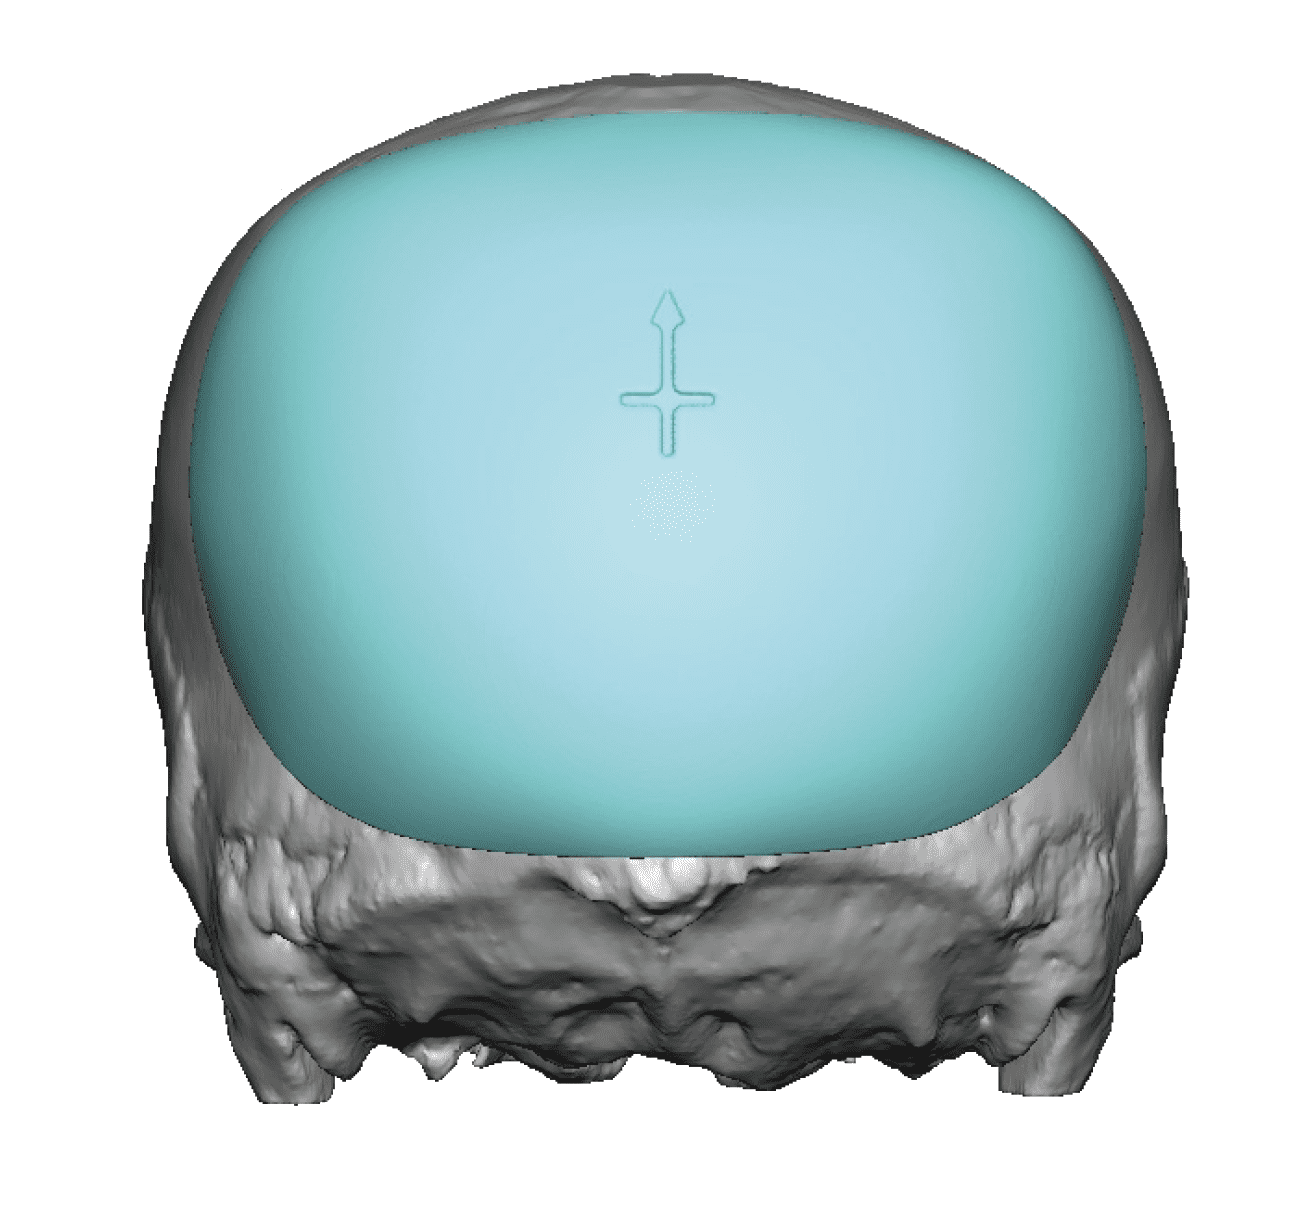

Desire for change of head shape from front view form an inverted V shape to a rounder and wider head shape.

Placement of custom extended forehead-temporal implants through incisions in the crease behind the ear. (he had a prior back of head skull implant which is green in the implant designs and which the head widening implants partially covered it)

Desire for change of head shape from front view form an inverted V shape to a rounder and wider head shape.

Placement of custom extended forehead-temporal implants through incisions in the crease behind the ear. (he had a prior back of head skull implant which is green in the implant designs and which the head widening implants partially covered it)